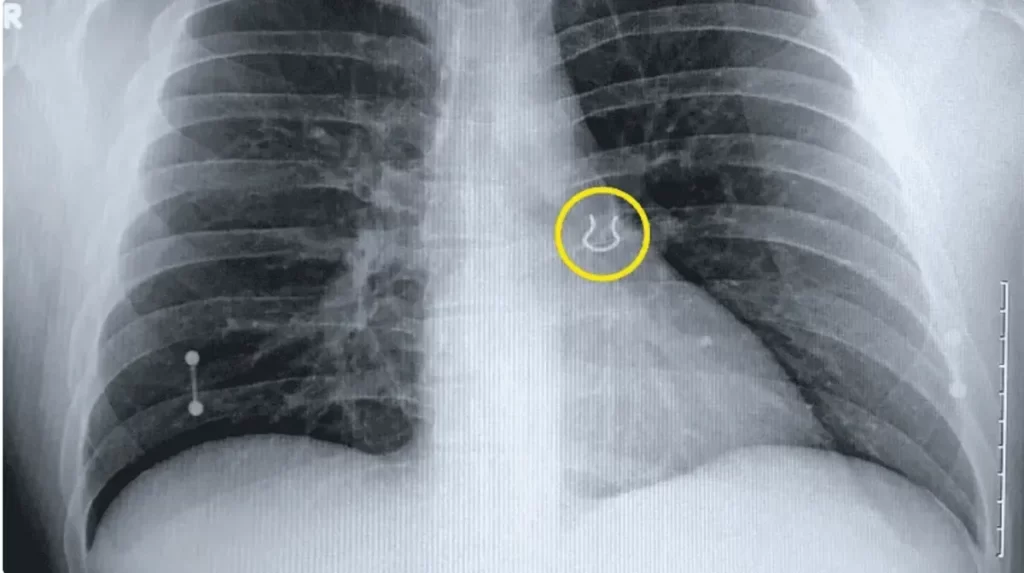

Joey Lykins, un estadounidense adicto a los piercings de 35 años, sorprendió a los médicos de guardia que descubrieron la razón detrás de su repentino problema respiratorio: encastrado en su pulmón izquierdo, encontraron el piercing nasal que perdió hace cinco años.

El viaje respiratorio de Lykins comenzó hace cinco años, después de que el nativo de Cincinnati, que cuenta con 12 perforaciones a lo largo de su cuerpo, se despertara un día sin su aro nasal. «Me desperté y mi perforación del tabique ya no estaba, y no pude encontrarla en ningún lado», describió.